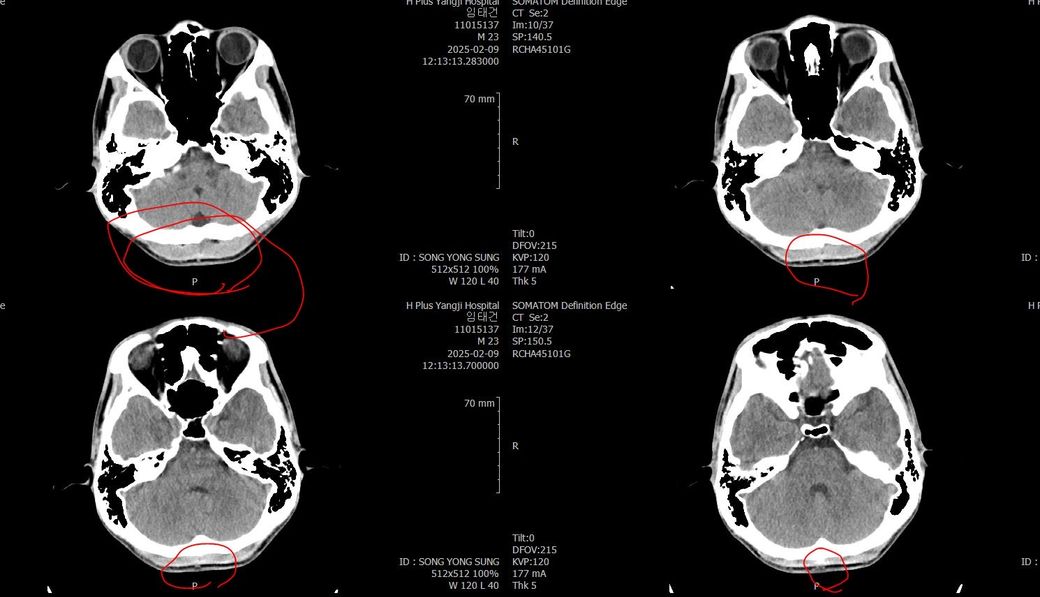

두개골 수술 또는 골절 의심되는 상황인데 엑스레이와 ct사진을 한번 봐주실 수 있나요?

2~3일 정도 기억이 없었는데 그때 머리를 다쳤는지 바로 x-ray와 ct를 찍어봤는데 한번 봐주실 수 있을까요? 진단 목적이 아닌 확인 목적입니다

빨갛게 동그라미 친 곳은 금속물질이 의심도는 부근입니다

• 3번 째 사진